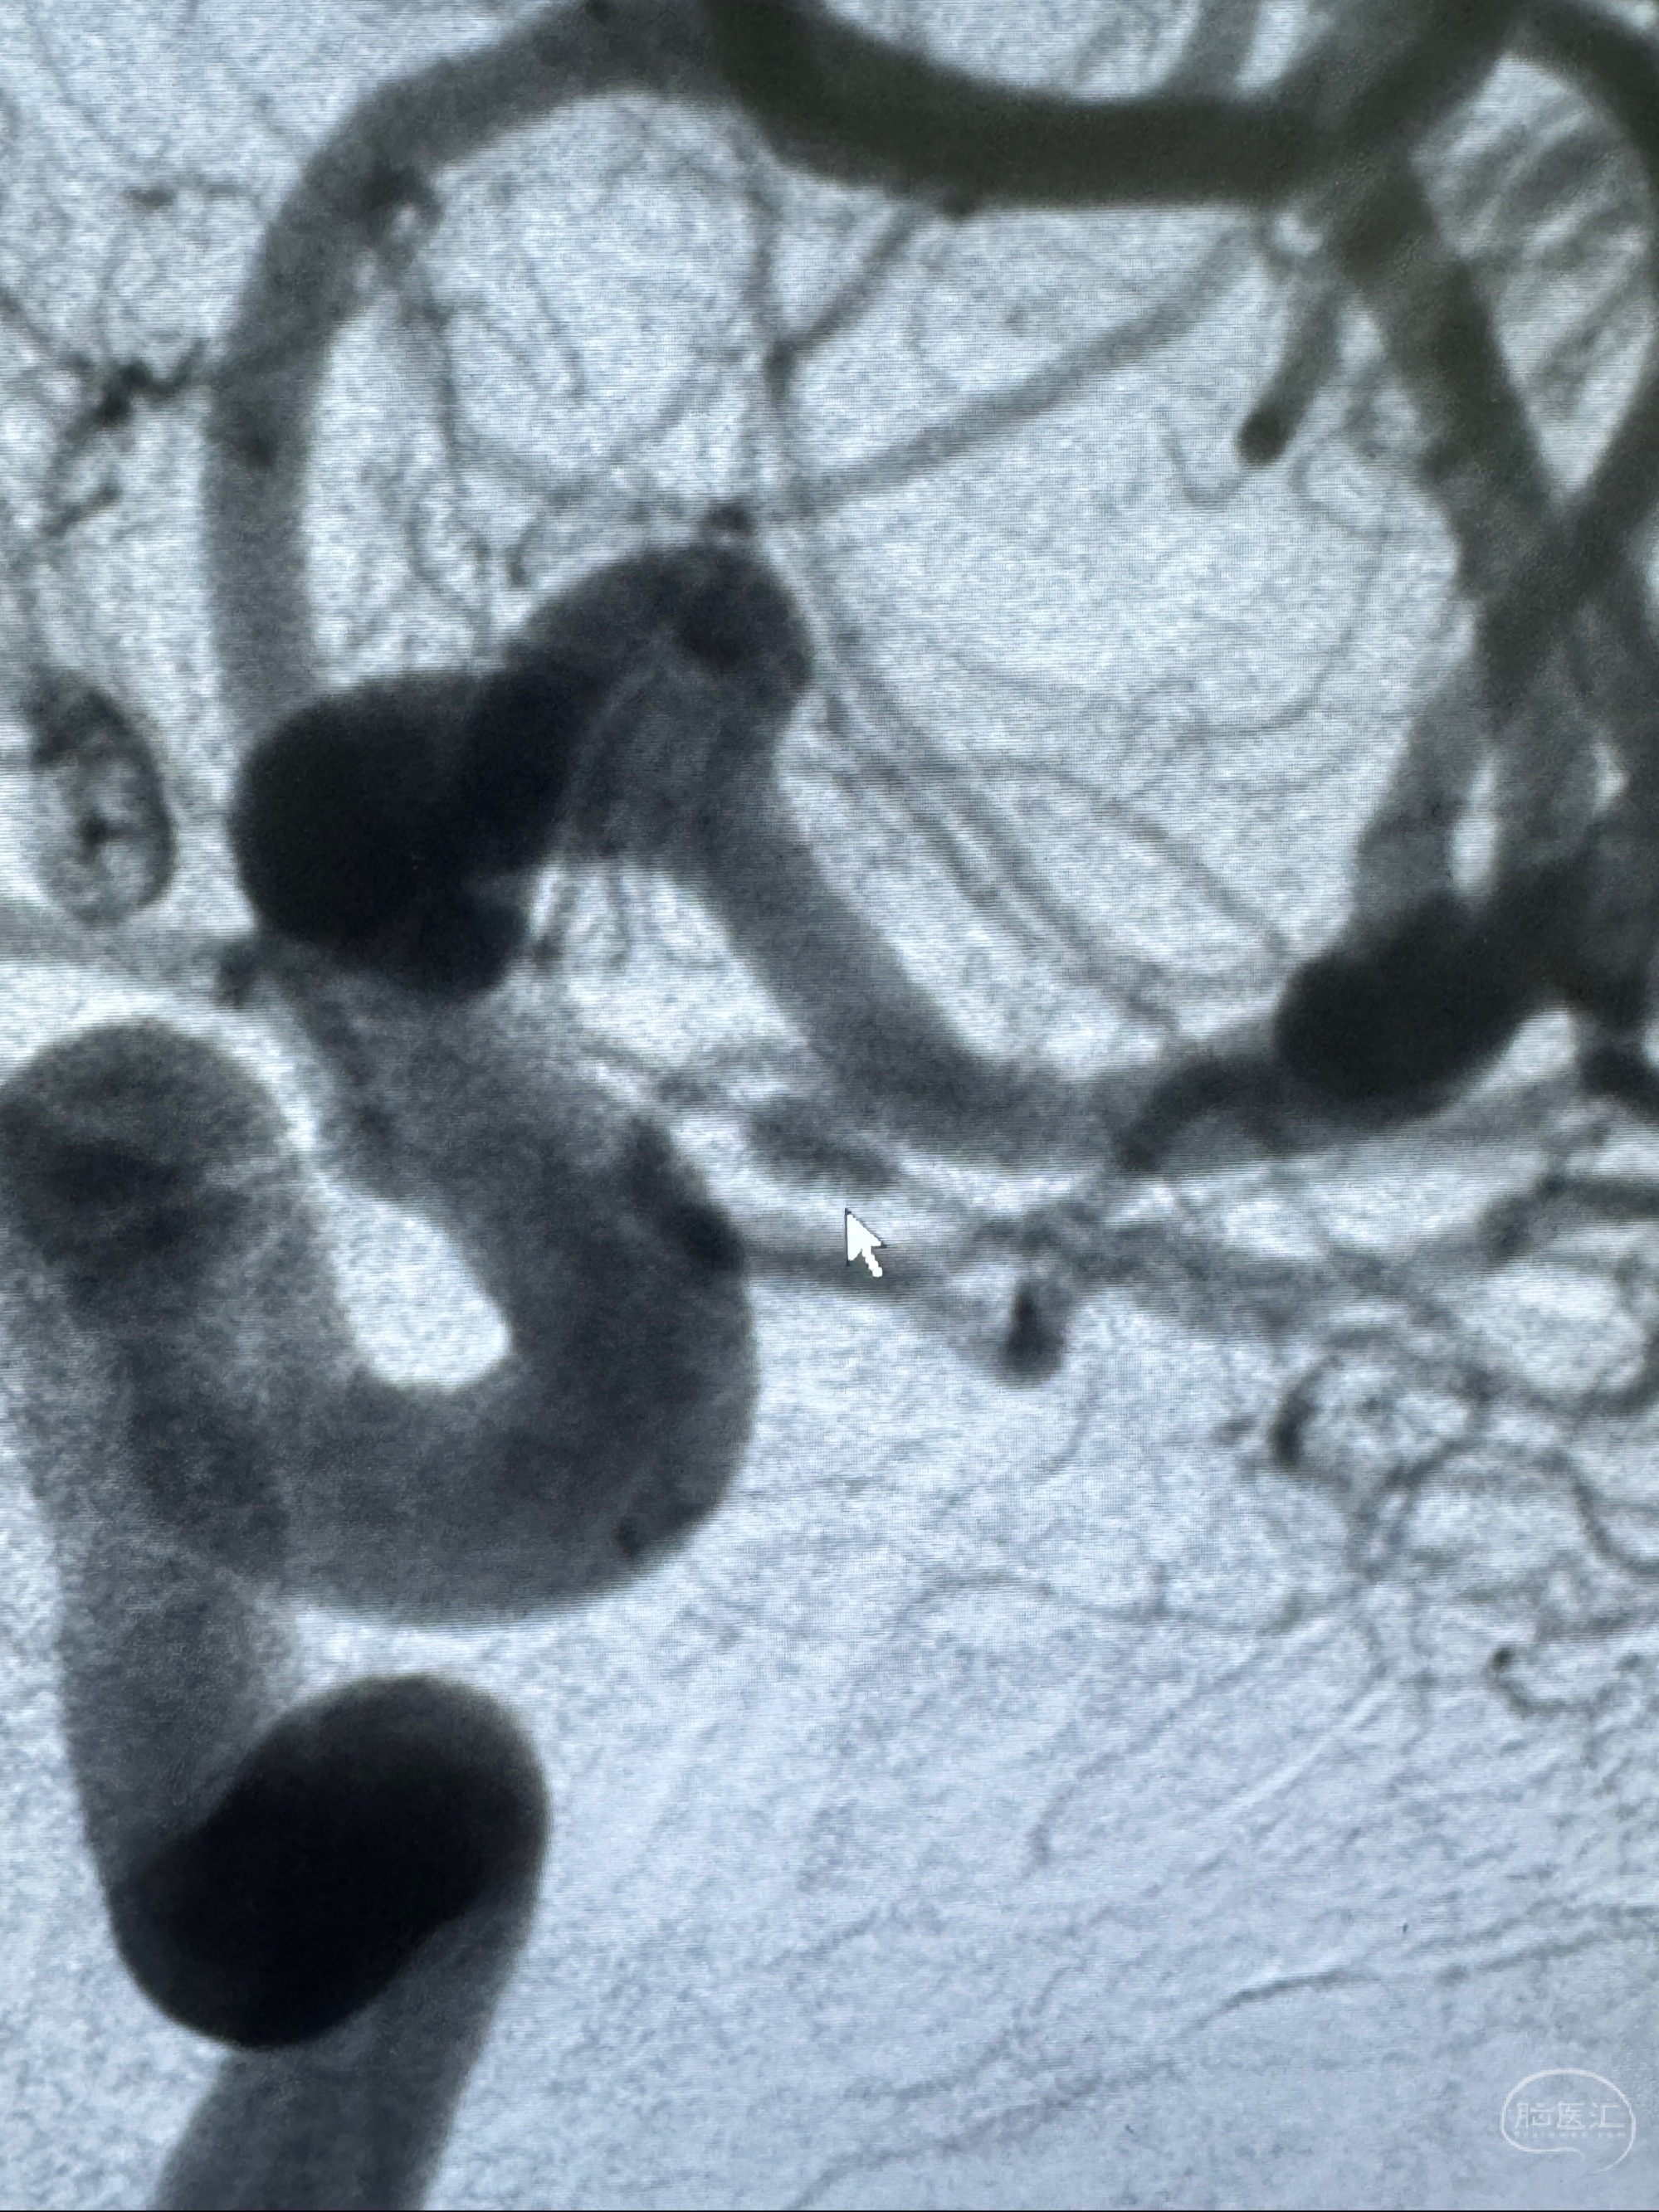

2023-12-04全麻下行支架辅助治疗

S-AB4-20mm

麻醉苏醒佳,遵嘱动作

术后即刻CT